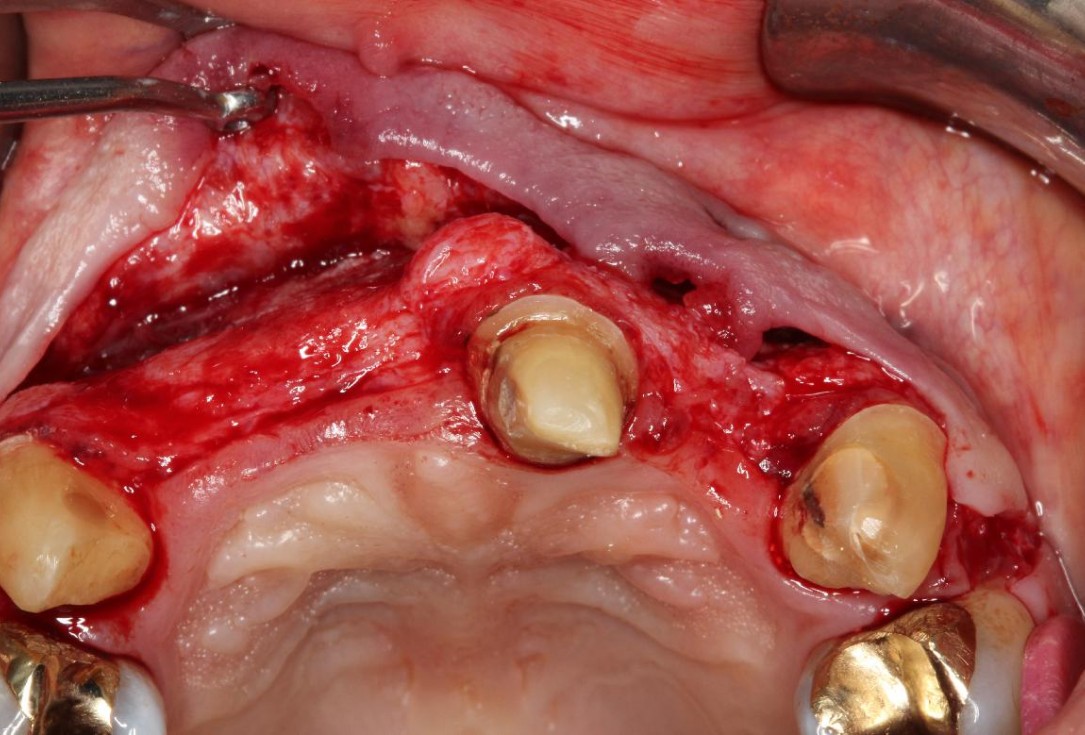

1/5 - Initial clinical situationPre-prosthetic soft tissue augmentation of the ridge contour with mucoderm®- Dr. F. Rathe

Initial clinical situation showing severe soft tissue loss

Initial clinical situation